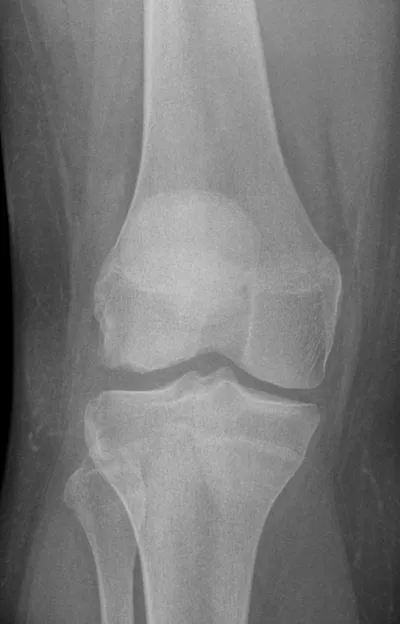

OCD Radiology Images

This collection contains 2 radiology images related to ocd, including various imaging modalities such as X-rays, MRIs, CT scans, and ultrasound images commonly used in medical diagnosis and education.